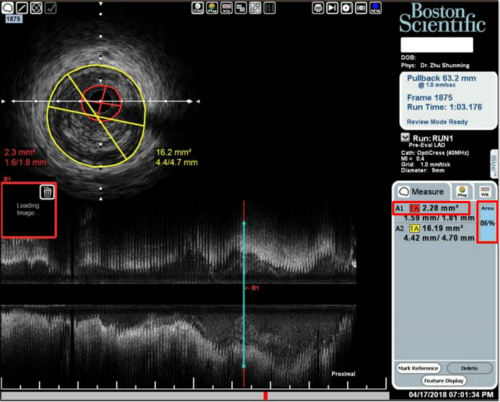

心绞痛疾病的凶险众所周知,如未及时有效治疗,随时有生命危险。61岁的张先生,因胸痛入院,被诊断为不稳定心绞痛,行冠脉造影提示左前降支、右冠状动脉均有一处不稳定斑块,血管堵塞面积较大。为了精准施治,心内科陆卫红主任、黄勇先主任为患者进行了血管内超声检查,发现患者左前降支管腔面积剩余50%,而右冠状动脉管腔面积剩余仅有20%,血管堵塞面积大,病情易变,需及时处理,否则有生命危险。陆卫红主任立即为患者制定了支架植入的手术治疗方案,手术非常顺利。

血管内超声(IVUS)技术可简单理解为通过导管技术将微型超声探头送入血管腔内,显示血管横截面图像,从而提供在体血管腔内影像。通过IVUS的应用不仅可以了解管腔的形态,还能直接显示管壁的结构,了解管壁病变的性质,很大程度上弥补了单纯冠脉造影对冠脉病变判断的不足,被认为是血管检查新的“金标准”。可为医生确定最合适的介入治疗方案,准确选择支架大小,确定支架的位置及扩张后与冠脉管壁贴壁是否良好,并可预测术后再狭窄的发生。